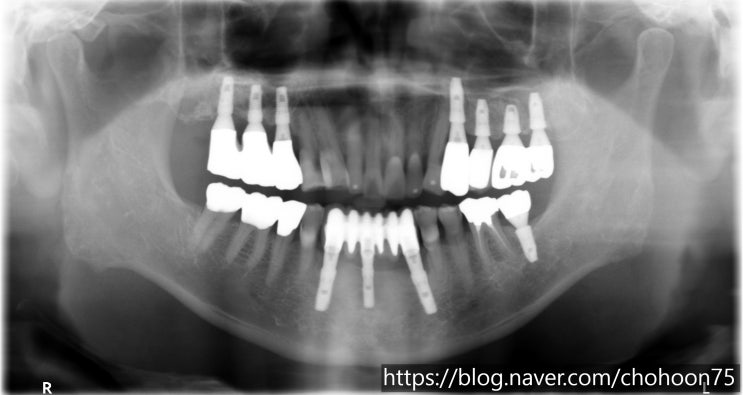

[조훈치과] 골다공증, 심혈관질환자의 임플란트 식립 치료 증례

골다공증, 심혈관 질환을 앓고 있어도 임플란트가 가능할까요? 골다공증은 정상적인 뼈와 비교할 때 골밀도...